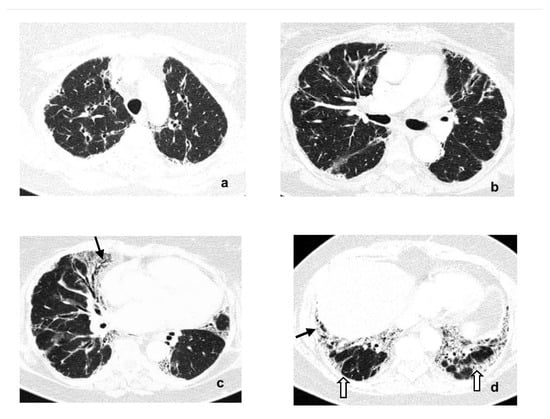

2. Case Report